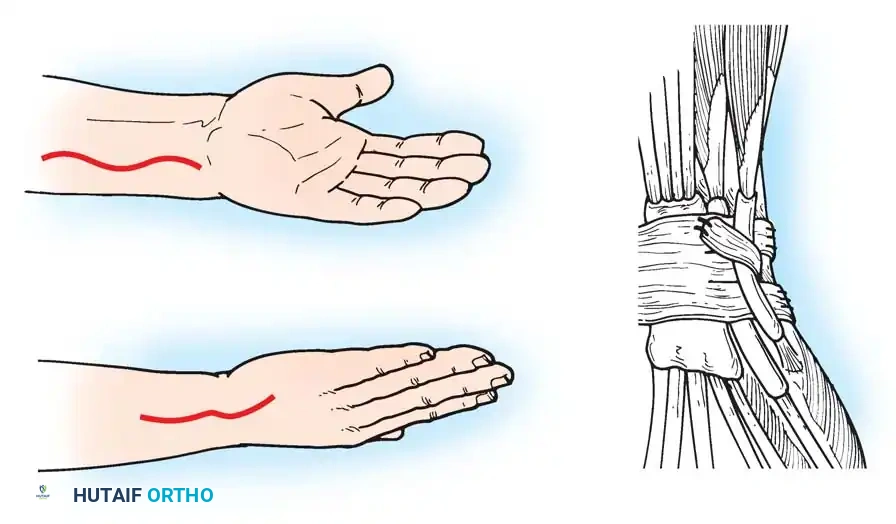

In cases of severe instability or concomitant ECU subsheath disruption, open capsular repair and ECU stabilization are required.

Open repair of the dorsal capsule and TFCC, ensuring robust closure and stabilization of the ulnar-sided structures.

Stabilization of the ECU tendon and subsheath, a critical step in addressing complex ulnar-sided wrist trauma.

1. Approach: A longitudinal incision is made over the subcutaneous border of the distal ulna. The interval between the ECU and flexor carpi ulnaris (FCU) is utilized.